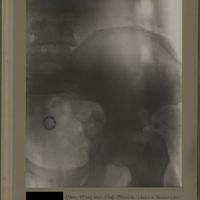

0117 - Page 5 - [Radiographie du bassin]0117 - Page 5 - [Radiographie du bassin]

0167 - Page 55 - [Radiographie du bassin]0167 - Page 55 - [Radiographie du bassin]